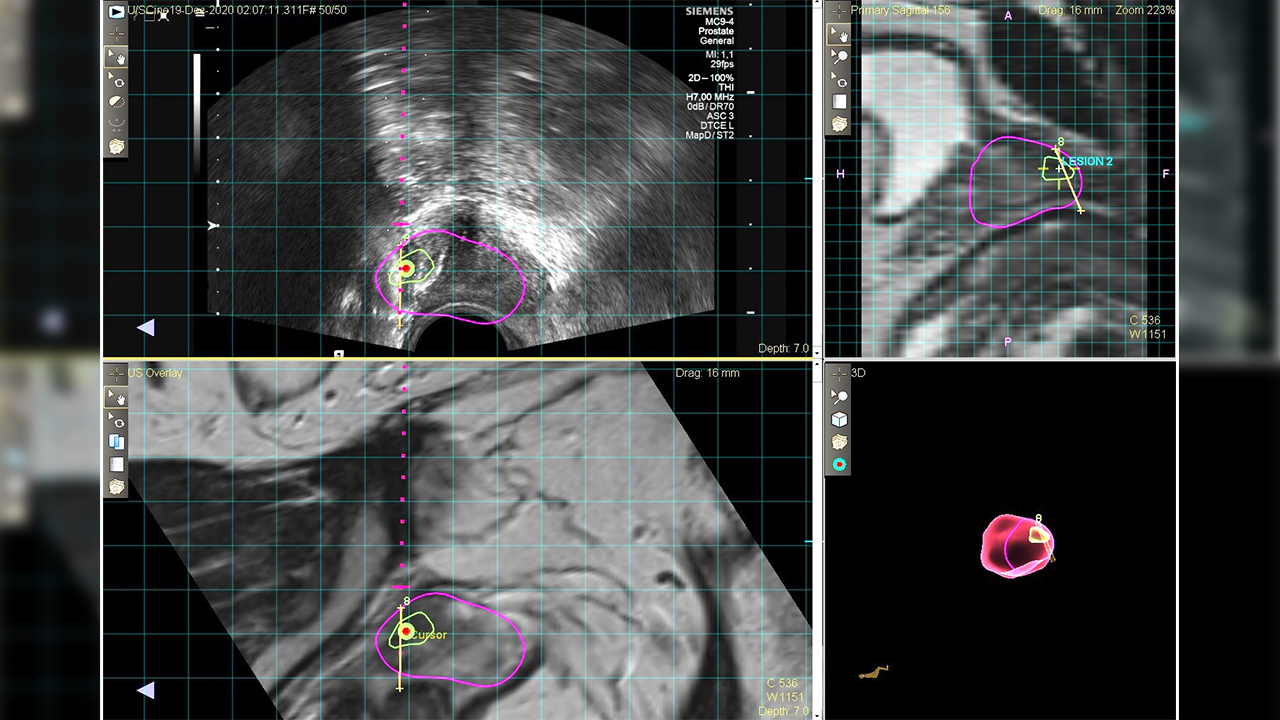

Op. Dr. Emir Akıncıoğlu, sözlerine şöyle devam etti: “MR Füzyon Biyopsi cihazıyla klasik biyopside atlanabilecek olan kanser odakları başarılı şekilde tespit ediliyor ve tam olarak belirlenen hedef noktalardan örnekler alınabiliyor. Bunun için önce MR filmi çekiliyor, sonrasında kanser şüpheli yerler belirlenerek füzyon biyopsi cihazına görüntüler yükleniyor. Ardından işlem esnasında gerçek zamanlı olarak ultrason ve MR görüntüleri örtüştürülüyor. İşlem sırasında şüpheli yerlerden tam isabet ile örnekleme yapılabiliyor. Hastalıklı prostatlı dokularının gözden kaçırılması riskini neredeyse sıfıra indiriyoruz. Bunun için teknoloji ve tecrübe gerekiyor. Biz de ekip olarak son bir yıl içerisinde 100’den fazla hastaya başarıyla bu işlemi uyguladık. En yüksek standartlarda hastalarımıza hizmet vermeye de devam ediyoruz”